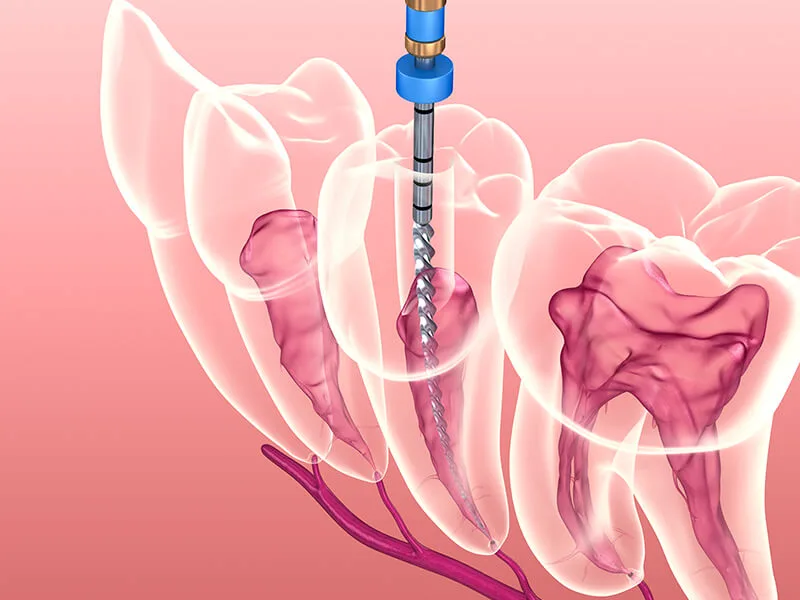

Buscar por um consultório endodontia perto de mim é uma decisão estratégica que une cuidado técnico e praticidade.

A proximidade facilita o acesso a tratamentos vitais, como o tratamento de canal, essencial para salvar dentes comprometidos e cessar quadros de dor aguda.

A praticidade nas consultas é um diferencial para quem possui uma agenda cheia. Visitar um consultório endodontia perto de mim permite que o tratamento não seja negligenciado, assegurando que a infecção seja removida e o dente preservado sem grandes alterações no seu roteiro diário.

Tecnologia Acessível: Unidades regionais modernas oferecem exames digitais e microscopia operatória;